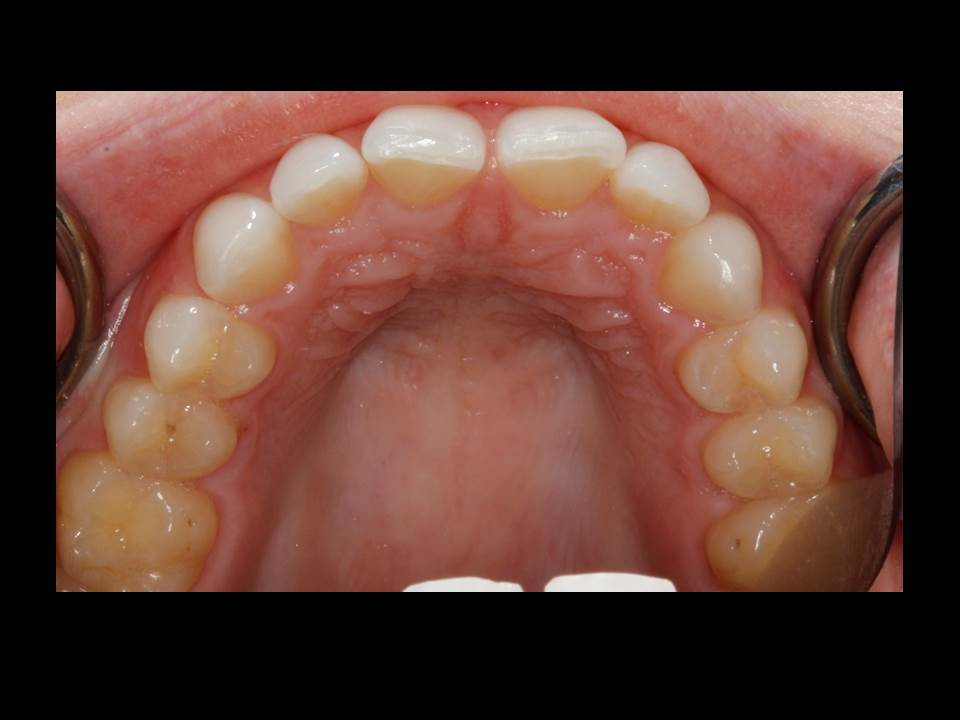

October is National Dental Hygiene Month, and the team at Delmarva Dental Services in Maryland is offering guidance on how to maintain healthy teeth and gums. Salisbury, MD – The… Read More